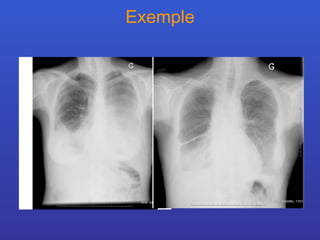

Exemple

Syndromes radiologiques Syndrome pleural

Définition: Le syndrome pleural englobe les signes qui traduisent la présence de liquide, d’air ou de tissu anormal dans l’espace pleural limité par les deux feuillets. Critère radiologiques L’aspect radiologique varie en fonction : position ( zones la plus déclive ) quantité de liquide localisation ( interlobaire ou scissural ) degré d’organisation ( épanchement cloisonné )